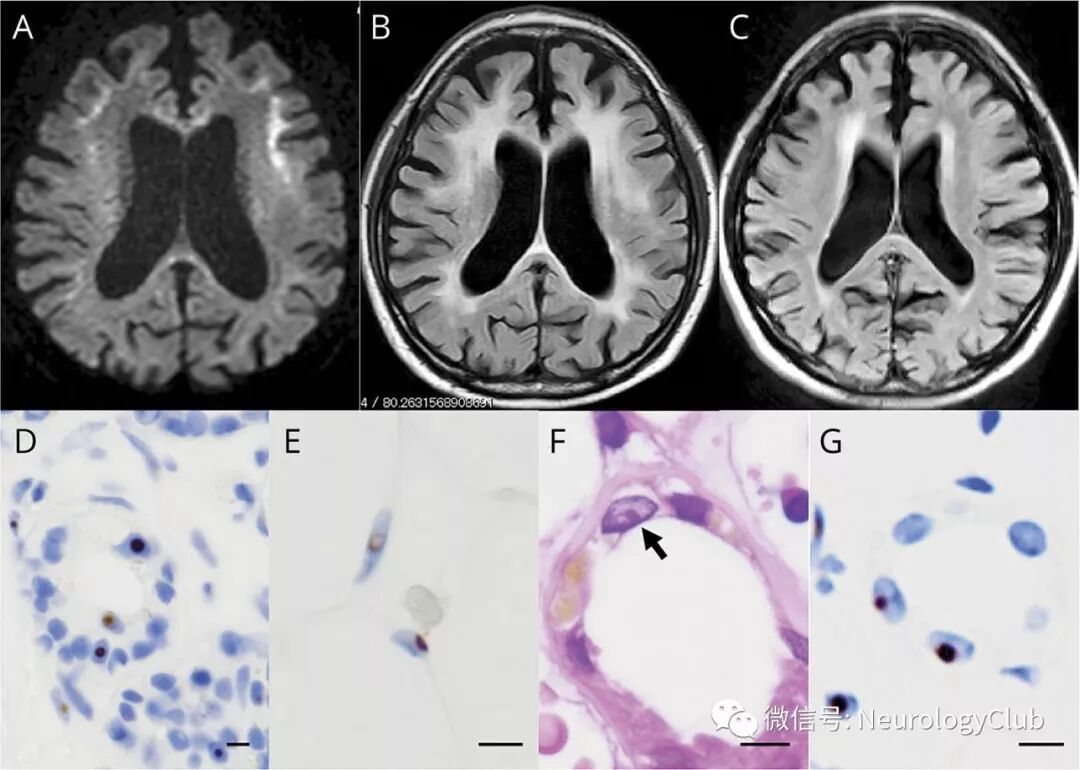

68岁日本男性,表现为双手震颤2年。既往12年前行肾活检诊断为系膜增生性肾小球肾炎。患者双上肢可见轻微的位置性和意向性震颤。没有发现其他神经系统异常,如小脑性共济失调,痴呆,锥体系和锥体外系症状,简易精神状态检查量表得分为30/30。除蛋白尿外,血液检查和尿液分析结果正常。磁共振FLAIR可见弥漫白质高信号,DWI可见皮髓质交界区线样高信号病变(图A-B)。6年前的FLAIR已有轻微的脑白质病变(图C)。但当时没有行DWI序列。

皮肤活检标本可见成纤维细胞,汗腺细胞和脂肪细胞中抗p62抗体阳性的嗜酸性透明核内包涵体(图D-E)。可诊断为NIID。对12年前肾活检保留的标本重新检查发现肾小管细胞内存在类似的核内包涵体(图F-G)。

(图:A:DWI可见皮髓质交界处线样高信号病灶;B:FLAIR可见白质弥漫性高信号;C:6年前的FLAIR序列已有轻微的脑白质病变;D-E:皮肤活检:皮肤汗腺[D]和脂肪细胞[E]p62免疫组织化学染色阳性;F-G:12年前的肾活检:HE染色可见肾小管细胞内嗜酸性透明核内包涵体[F,箭],抗p62抗体阳性[G];比例尺=10μm